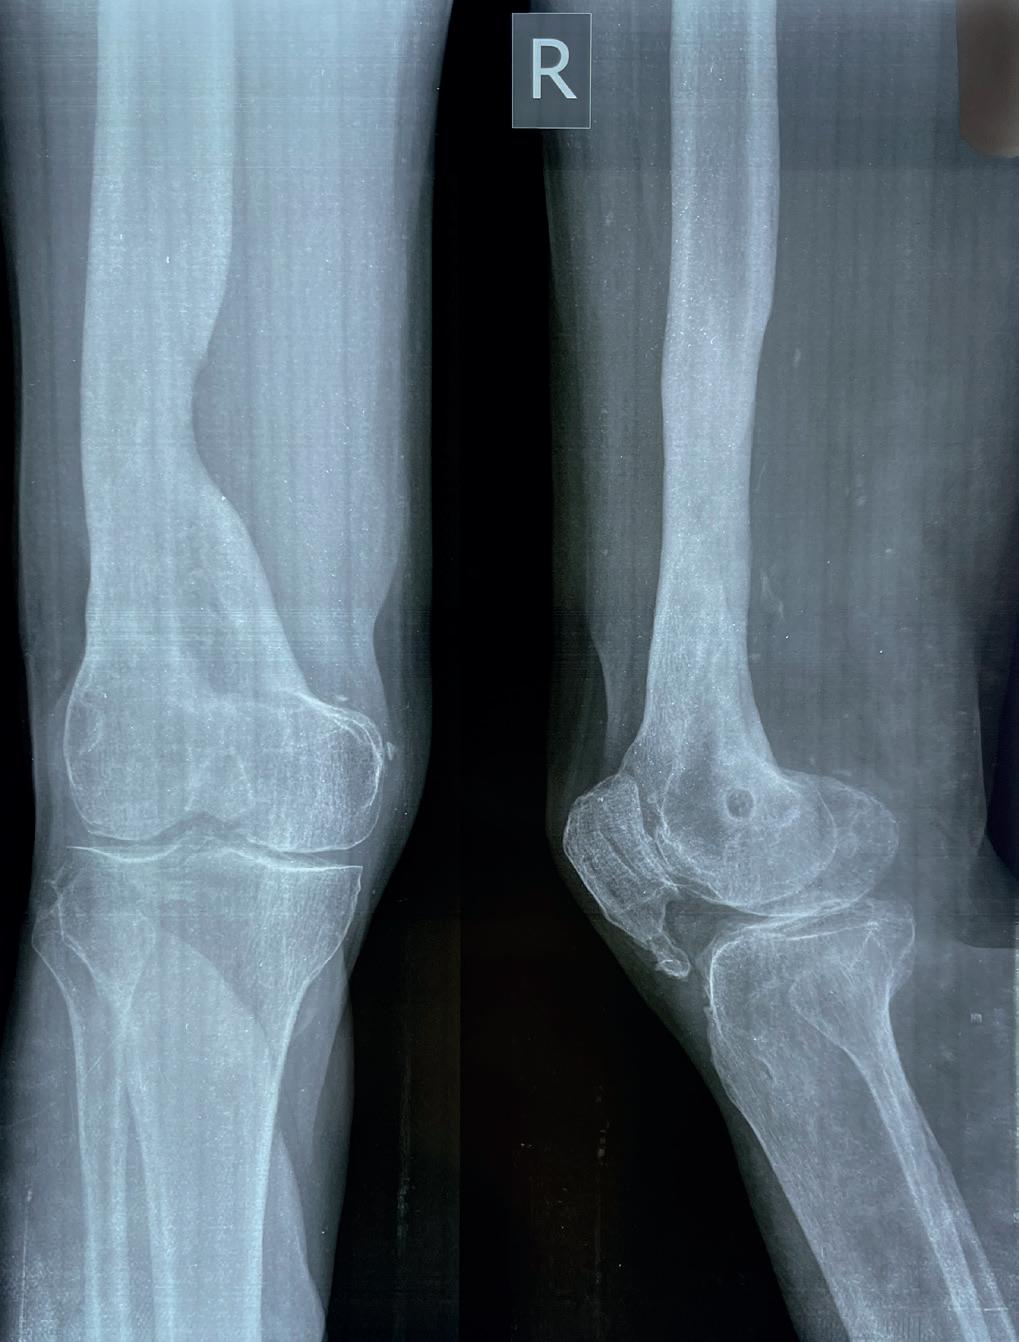

En annen pasient som jeg traff hadde tilbrakt sine dager på åkeren. Siden klimaet er varmt, til tross for høyden, hadde han bare slippers på seg. Han hadde vært litt uforsiktig, snublet og falt ned en skrent. Og terrasser med skrenter er det mange av i Nepal. Han slo venstre ankel hardt mot en stein. Han hadde pådratt seg et stort sår over mediale malleol og klarte bare så vidt å tråkke på venstre fot. Han var alene på åkeren. Det var over to kilometer til nærmeste hus og vei. På en eller annen måte klarte han å komme seg til en vei, men det var blitt kveld da han fant en bil som kunne kjøre ham ned til sykehuset. Midt på natten ankom han akuttmottaket, etter flere timers kjøring. Vakthavende LIS var litt fortumlet da han så pasienten, sa til sykepleierne at de skulle skylle såret og legge pasienten inn. På morgenmøtet kommende dag ble alvorlighetsgraden av skaden underrapportert og det tok flere timer før pasienten ble tatt inn på operasjonsstuen, godt ett døgn etter skadetidspunktet. Han hadde en åpen ankelfraktur som fortsatt var ganske forurenset (Bilde 6). På operasjonsstuen ble ankelen skrubbet

fri for alt av fremmedlegemer og annet smuss, skylt og man fjernet dødt vev. Heldigvis hadde vi en ledig operasjonsstue, Ketamin og en tålmodig pasient. Gjentatte ganger ble pasienten tatt inn på operasjonsstuen for debridement de påfølgende ukene. Vi prøvde oss også på en vakuumbandasje-behandling – jeg hadde tatt med noen plastfolier fra Norge og på sykehuset i Okhaldhunga har de sug i veggen. Dessverre viste det seg fort at undertrykket var for ustabilt og vakuumbandasjen fungerte ikke. Vi fortsatte derfor med å gjennomføre regelmessig debridement, hver andre eller tredje dag (8). Såret tilhelte langsomt uten infeksjon, og til slutt kunne vi legge på delhud (Bilde 7). Etter seks uker var også frakturen grodd, den eksterne fiksasjonen kunne fjernes og pasienten ble sendt hjem igjen til gården sin, med to fungerende bein.

I Nepal har man ikke alltid og overalt dyre spesialbandasjer eller vakuumassistert behandling tilgjengelig. Da må man tilbake til den gode gamle metoden med debridement: fjerning av dødt, skadd og infisert vev (9). Og dette gjentatte ganger, helt til det bare er friskt vev igjen.